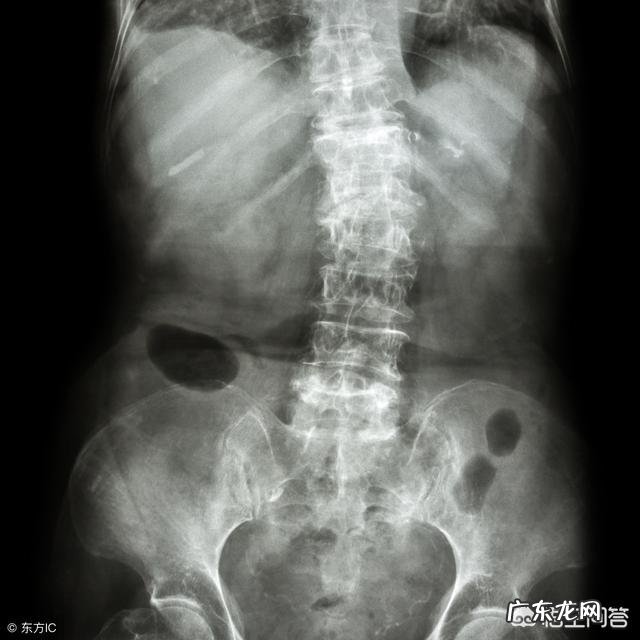

通常在给这部分患者做触诊的时候会发现,他们多数人会存在腰肌劳损、腰椎小关节错位、腰椎间盘突出症,这也是导致腰椎病频繁发作的主要因素 。

也就是说,平常腰痛,最常见的原因还主要是三个:diyi个是腰肌劳损,第二个是腰椎小关节紊乱,第三个是腰椎间盘突出症 。

腰椎间盘突出症

可能不少人会认为腰椎间盘突出症?不是腿疼吗?其实,如果一个人没有诱因的反复性发作的腰疼可能是腰椎间盘突出症的一个特殊性表现 。